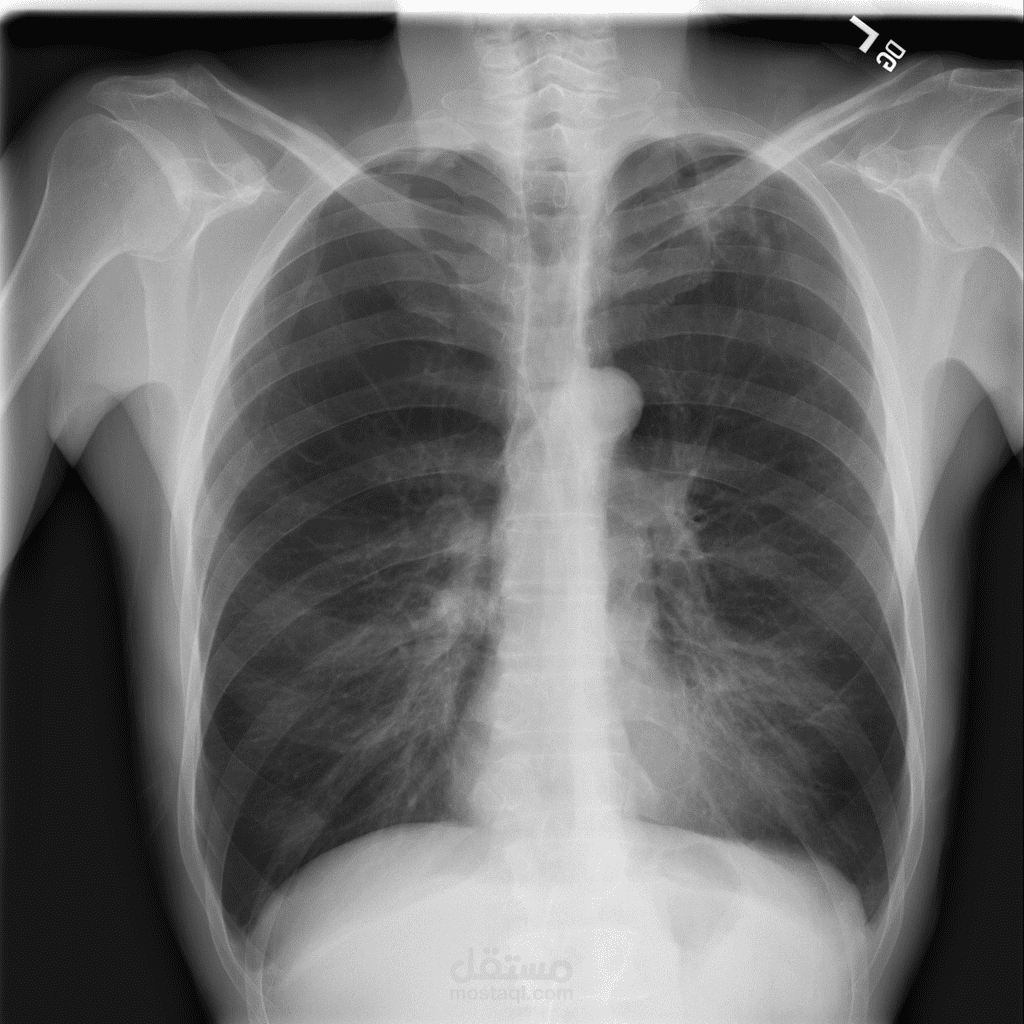

يهدف هذا المشروع إلى تطوير نموذج دقيق لاكتشاف الالتهاب الرئوي من صور الأشعة السينية (X-ray) باستخدام تقنيات التعلم العميق. تم استخدام نموذج EfficientNetB0 كنموذج أساسي، حيث أظهر أداءً ممتازًا وحقق دقة بلغت 99% على مجموعة البيانات المستخدمة. كما تم أيضًا استخدام نموذج VGG19 كجزء من عملية المقارنة والتجريب بهدف تعزيز الأداء وتحليل النتائج.

هذا المشروع يُظهر فعالية النماذج الحديثة مثل EfficientNetB0 و VGG19 في الكشف المبكر عن الالتهاب الرئوي، مما يعزز من فرص التشخيص السريع والدقيق في المجال الطبي.